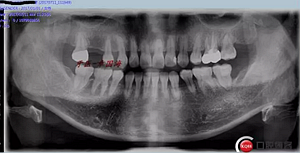

附另外一種植前后圖: